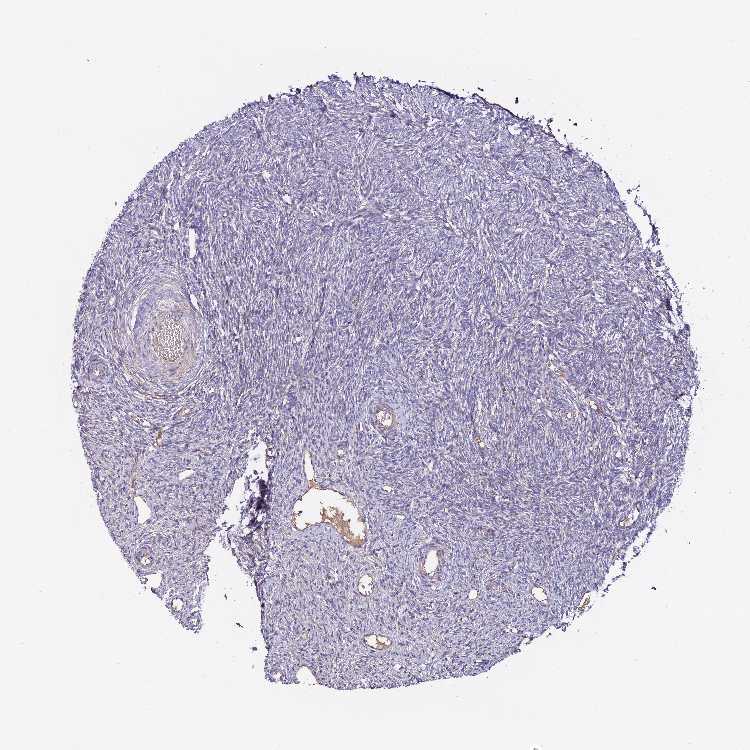

Antibody staining in the annotated cell types in the current human tissue is reported as not detected, low, medium, or high. This score is based on the staining intensity and fraction of stained cells.

Information about each individual sample is listed below, including gender, age, a tissue section image and estimated fractions of cell types. pTPM (transcripts per million) values give a quantification of the gene abundance which is comparable between different genes and samples.